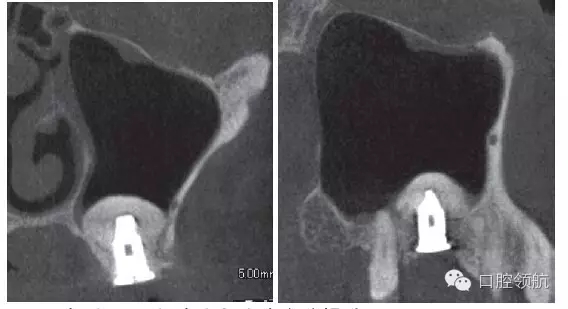

拔除(左上第六顆牙)后,抗生素(500mg)口服1周。術(shù)后4周的CBCT顯示,上頜竇黏膜增厚明顯改善(圖3)。

圖3 拔牙后4周,上頜竇黏膜增厚消失,但仍有殘留牙槽窩。

在行植入手術(shù)時,手術(shù)前一定要根據(jù)CBCT影像確認(rèn)中鼻道(ostimeatal complex,OMC)的鼻腔形態(tài)(鼻中隔彎曲的狀態(tài),是否是泡狀中鼻甲,下鼻甲是否肥大)和換氣功能是否正常。該病例OMC的換氣功能正常,鼻中隔無彎曲,對右側(cè)上頜竇影響很小。

從矢狀面觀察上頜竇狀態(tài),拔牙后在牙槽窩還沒有消失,垂直提升量不是很多,視野清晰的情況下,選擇經(jīng)牙槽嵴頂入路。